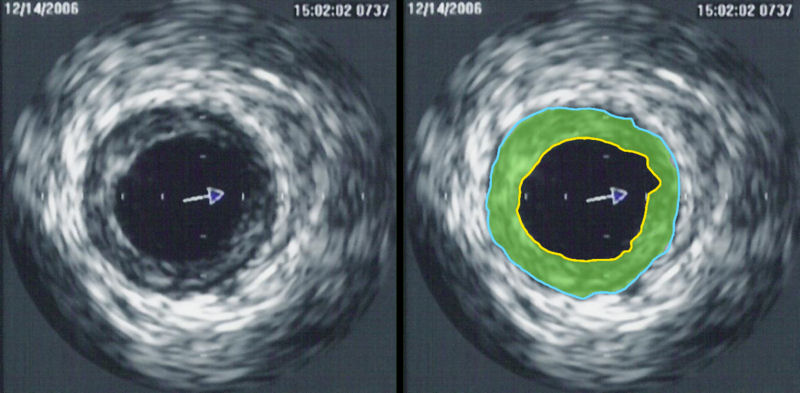

back Intravascular ultrasound image of a coronary artery